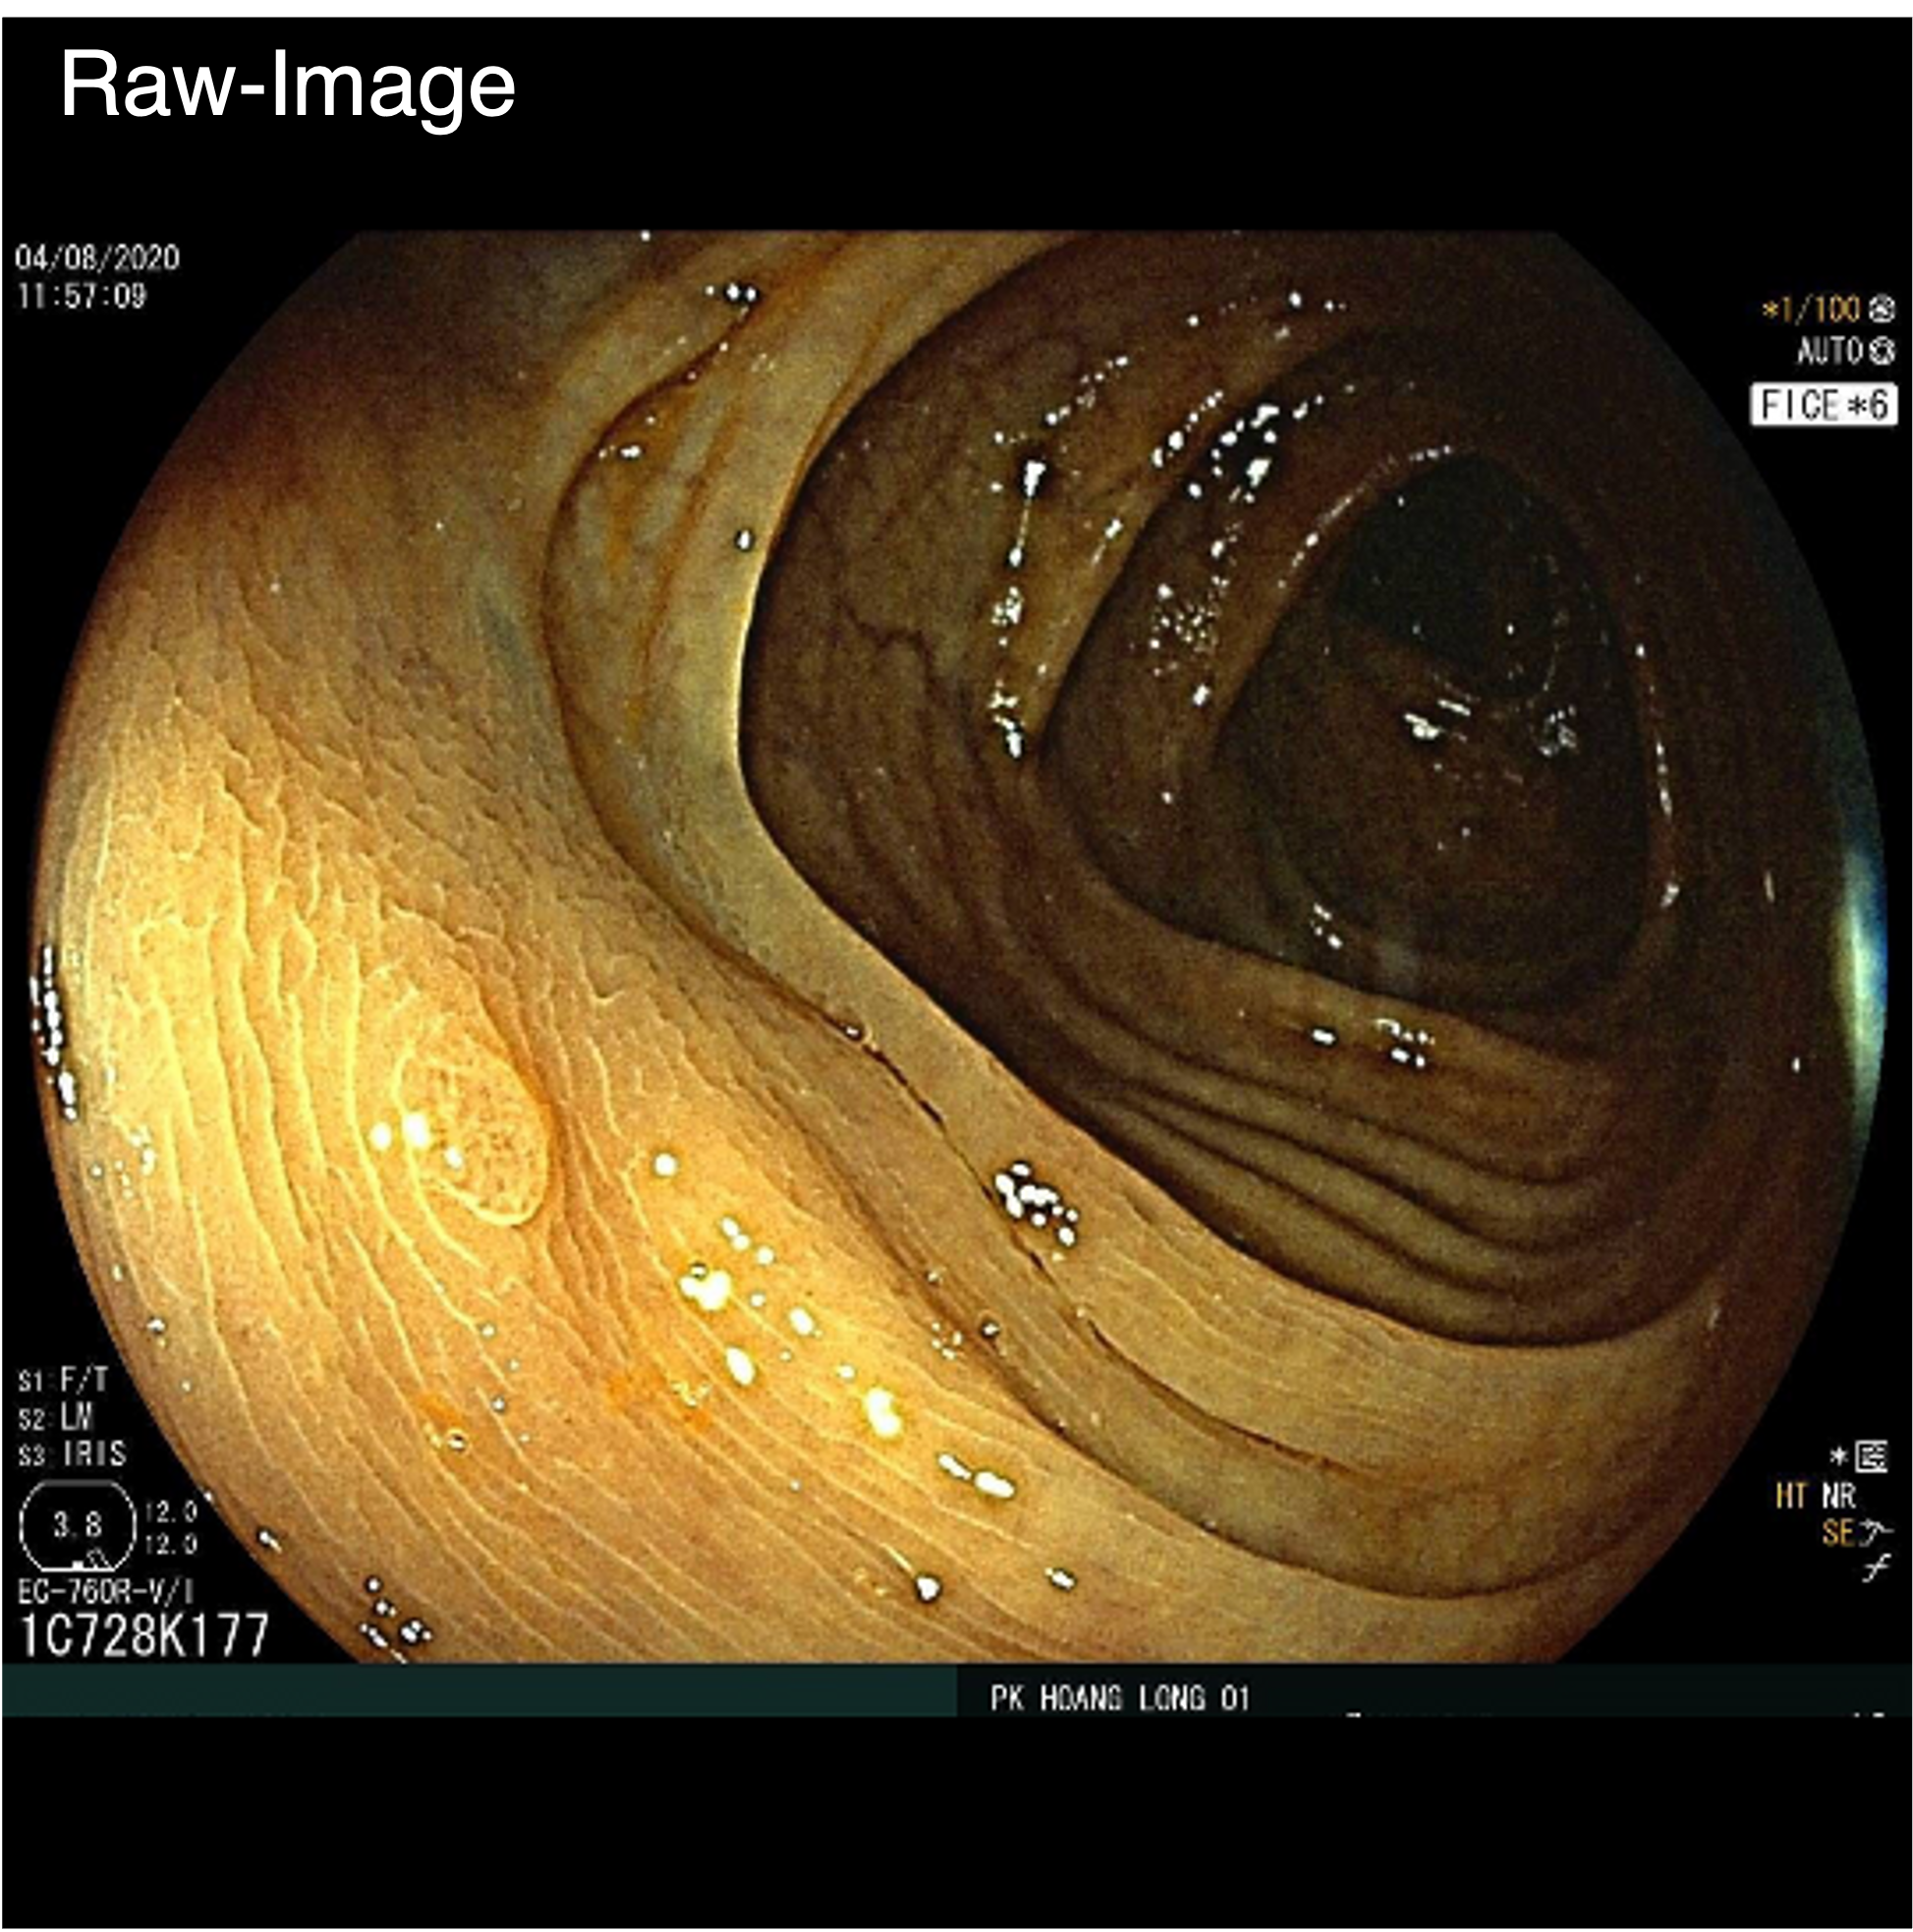

Qualitative comparison results

Qualitative Comparison. Comparison results between various state-of-the-art detection methods and the proposed method is shown above. Our method effectively leverages modality context to significantly enhance anomaly localization (red), compared to baseline results (blue). Ground truth bounding boxes are green. For cases where the bounding boxes are small, insets show an enlarged view of the highlighted yellow region.